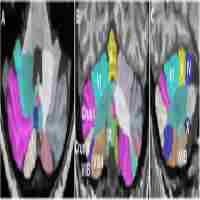

Regional cerebral blood volume ( rCBV ) bias voxel-based morphometry ( VBM ) in an animal study

| Abstract | VBM result without rCBV 4443 Regional cerebral blood volume (rCBV) bias voxel-based morphometry (VBM) in an animal study Dirk Ernst Cleppien, Lei Zheng, Claudia Falfan-Melgoza, Barbara Vollmayr, Wolfgang Weber-Fahr, and Alexander Sartorius RG Translational Imaging, Department of NeuroImaging, Central Institute of Mental Health, Medical Faculty Mannheim, University of Heidelberg, Mannheim, Germany, Experimental Radiation Oncology, Medical Faculty Mannheim, University of Heidelberg, Mannheim, Germany, Department of Psychatry and Pschotherapy, Central Institute of Mental Health, Medical Faculty Mannheim, University of Heidelberg, Mannheim, Germany, RG Animal Models in Psychiatry, Central Institute of Mental Health, Medical Faculty Mannheim, University of Heidelberg, Mannheim, Germany |